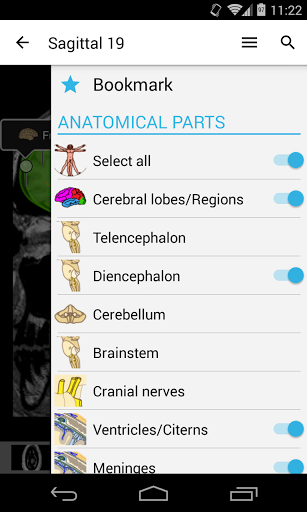

- يمكنك الآن إخفاء الهياكل واحداً تلو الآخر (زر جديد داخل نافذة الوصف المنبثقة) وعرضها مرة أخرى في القائمة الصحيحة

- وحدة جديدة: أطلس تشريحي للعمود الفقري القطني على التصوير المقطعي والأقراص الفقرية والمفصل القطني القطني في الأقسام المحورية والإكليلية والسهمي وعلى الصور ثلاثية الأبعاد الألمانية الآن معتمدة للهياكل التشريحية وضع بحث محدث (زرين جديدين في عرض التفاصيل للبنية وزر إغلاق بجوار تسمية الهيكل الذي تم البحث عنه) خطأ في البحث -Fix على بعض إصدارات Android الخلل الصغيرة الثابتة

- وحدة جديدة: أطلس تشريحي للعمود الفقري القطني على التصوير المقطعي والأقراص الفقرية والمفصل القطني القطني في الأقسام المحورية والإكليلية والسهمي وعلى الصور ثلاثية الأبعاد الألمانية الآن معتمدة للهياكل التشريحية وضع بحث محدث (زرين جديدين في عرض التفاصيل للبنية وزر إغلاق بجوار تسمية الهيكل الذي تم البحث عنه) الخلل الصغيرة الثابتة

- وحدتان جديدتان: الدماغ - TOF والأوعية الدموية الدماغية ، أطلس التشريح الوعائي العصبي الطبيعي لشرايين الدماغ على الأوعية الدموية الدماغية. - تم إعادة صياغة الواجهة. - تتوفر علامة تبويب جديدة باسم "QuickLinks" ، ترسل وحدات في أقسام من جسم الإنسان وتسمح لك بالسفر السريع إلى الوحدات التي تبحث عنها. الخلل الصغيرة الثابتة.